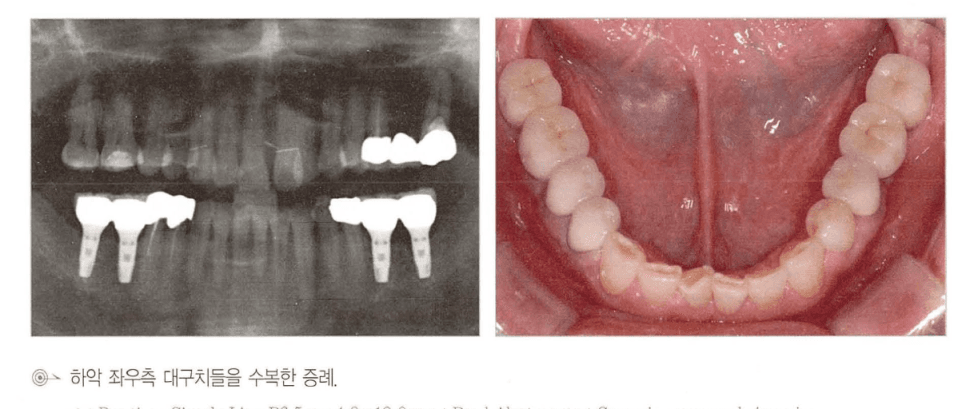

[그림 2] 상악 우측 대구치 구간을 임플란트 2개 + 중간 pontic 형태의 3-unit 브리지로 수복한 실제 임상 증례. 파노라마와 구강 내 사진에서 배치를 확인할 수 있습니다.

구치부 3개 상실이라고 해서 반드시 임플란트 3개를 모두 심어야 하는 것은 아닙니다. 양쪽 끝에 2개를 심고 중간을 pontic으로 연결하는 3-unit 설계가 임상에서 널리 쓰이며, 세 가지 실질적 이점이 있습니다.

- 수술 횟수·비용·회복 기간 감소 — 식립 개수가 줄면서 전신 부담이 작아집니다.

- 보철물 적합도 향상 — 임플란트가 너무 많이 나란히 배치되면 인상 정밀도와 패시브 핏 확보가 어려워집니다.

- 잇몸 건강에 유리 — 임플란트 사이 치간 유두(papilla)보다 임플란트–pontic 경계의 연조직 형태가 상대적으로 더 안정적입니다.

⚠️ 단, 상악 구치부처럼 골질이 약하거나 상악동 골이식이 필요한 증례에서는 교합력 분산을 위해 3개를 모두 심는 편이 안전합니다. “항상 2개 + pontic” 같은 규칙이 아니라 환자별 골질·교합력 평가가 우선입니다.